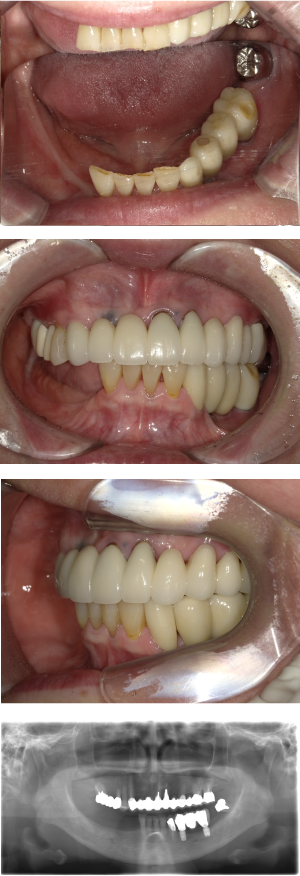

インプラント治療(左上5ソケット・GBR 右上2左上13GBR)

| 年代・性別 | 50代・男性 |

| 主訴 | 入れ歯だと咬めなくてつらい。 |

| 部位 | 上顎②1①2③4⑤Br |

| 治療期間 | 約9ヶ月 |

| 費用 | ¥1,794,100(税込) |